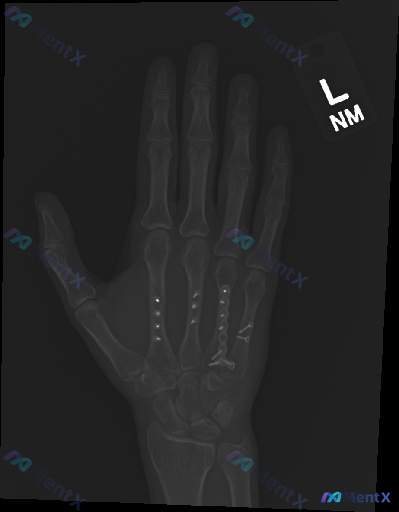

左手正位X光片,除了术后内固定还需要关注什么?

这是一个左手掌骨术后复查的影像学病例讨论。X光片显示第3、4、5掌骨存在金属内固定物,骨痂生长尚可;但围绕内固定系统的稳定性、是否存在隐匿风险,有多个观察与判断方向值得梳理。